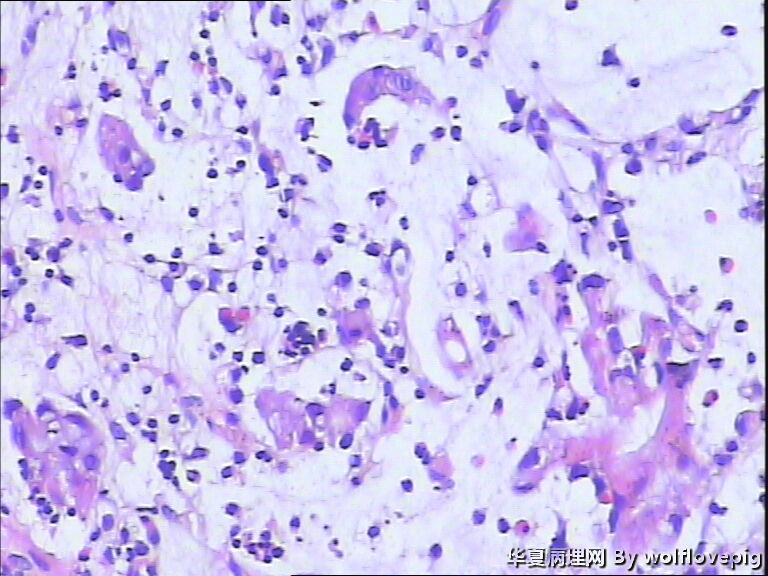

男,60y,胃窦呈结节样改变。

图1

黏液腺癌。

肿瘤中含有50%的细胞外黏液池,黏液中漂浮着散在或串珠状的癌细胞,癌细胞为富含黏液的柱状细胞及印戒细胞。